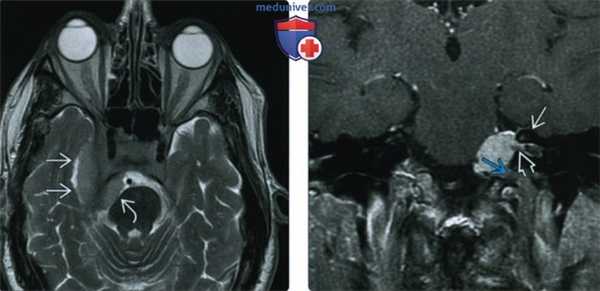

(Слева) При MPT Т1ВИ с КУ в сагиттальной проекции у переднего края большого затылочного отверстия определяется глобулярное объемное образование, смещающее продолговатый мозг кзади. Наличие фиксированного к твердой мозговой оболочке широкого основания свидетельствует в пользу менингиомы, а не какого-либо другого новообразования большого затылочного отверстия, например, шванномы.

(Справа) При МРТ Т1ВИ с КУ в аксиальной проекции определяется менингиома переднего края большого затылочного отверстия, лежащая медиальнее левой позвоночной артерии. Учитывая наличие в основании черепа большого количества критически важных сосудистых и нервных структур, резекция даже небольших новообразований может быть затруднена.

(Слева) МРТ, Т2-ВИ, аксиальный срез: в правом мостомозжечковом углу (ММУ) визуализируется объемное образование с четкими контурами, распространяющееся в правый внутренний слуховой проход.

(Справа) МРТ, постконтрастное Т1-ВИ, аксиальный срез: отмечается интенсивное и однородное контрастное усиление менингиомы в ММУ. (Слева) МРТ, Т2-ВИ, корональный срез: в области левой обонятельной луковицы определяется объемное образование изоинтенсивного по отношению к коре головного мозга сигнала с перифокальным отеком.

(Справа) МРТ, постконтрастное Т1 -ВИ, аксиальный срез: интенсивное и однородное контрастное усиление объемного образования, представляющего собой менингиому обонятельной борозды.